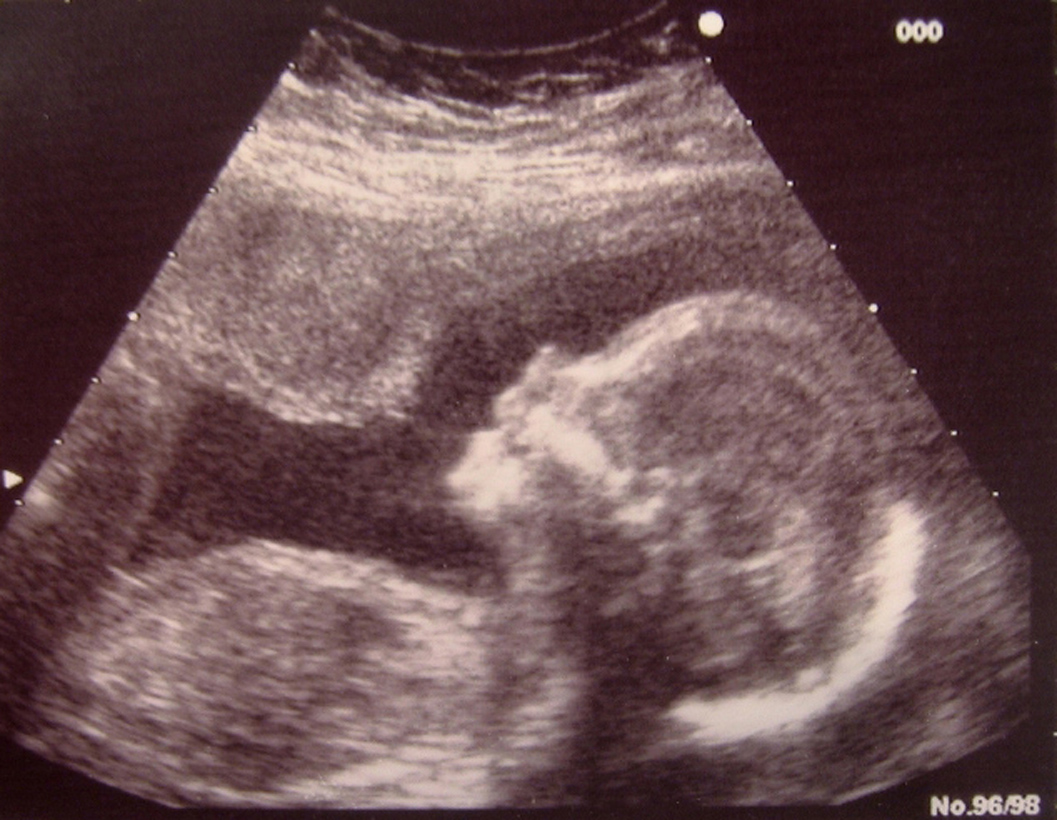

Bajo la ley del ultrasonido, a los médicos se les requiere presentar las imágenes de manera que las mujeres las puedan ver, aunque ellas tienen la opción de desviar la mirada si no quieren verlas. Los médicos enfrentan una multa de $100,000 por la primera ofensa y una multa de $250,000 por las subsiguientes ofensas.